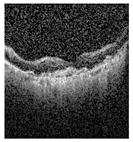

The publicly accessible dataset [27] encompasses detailed cross-sectional images of living patients’ retinas, which have been classified into four distinct categories: Normal, CNV, Drusen, and DME. These categories are visually represented in Figure 3. The dataset comprises a grand total of 84,492 images, distributed as follows: CNV contains 37,457 images, Normal contains 26,567 images, DME includes 11,600 images, and Drusen encompasses 8868 images.

Figure 3. Illustrative examples from the retinal image dataset are presented. Figure (a) showcasing Choroidal NeoVascularization, characterized by the presence of neovascular membranes (indicated by white arrowheads) along with associated sub-retinal fluid (marked by arrows). Figure (b) illustrates Diabetic Macular Edema, which manifests as intra-retinal fluid associated with retinal thickening (denoted by arrows). Figure (c) displays multiple instances of drusen (highlighted by arrowheads), while Figure (d) illustrates a normal, pristine retina with an undisturbed foveal structure and no signs of retinal fluid or edema.